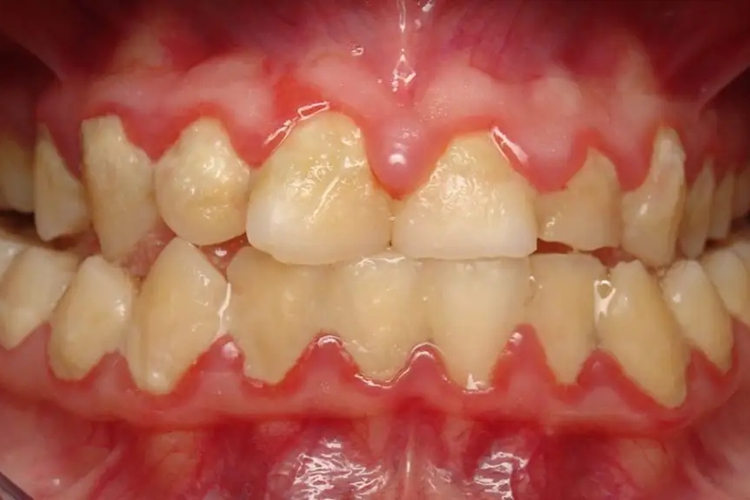

中度牙周炎牙周袋≤6mm,附着丧失3-4mm,X线片显示牙槽骨水平型或角型吸收超过根长的1/3,但不超过根长的1/2。牙齿可能有轻度松动,多根牙的根分叉区可能有轻度病变,牙龈有炎症和探诊出血,可见牙龈脓肿,也可有溢脓。